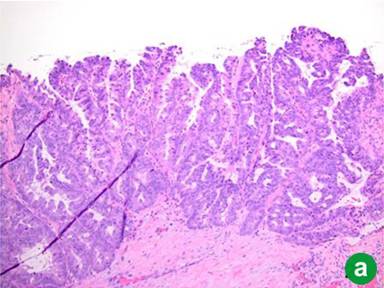

In 2011, four years after her original presentation, we performed a classic Whipple operation with a blood loss of 550 mL. Intraoperative frozen section of the common bile duct was negative for malignancy. The postoperative course was unremarkable and the patient was discharged to home 8 days later. Pathology report showed intraductal oncocytic papillary carcinoma 9 cm in greatest diameter, with 25 negative lymph nodes and microscopically negative surgical margins. The tumor showed diffuse high grade dysplasia and architectural complexity as well as mucin-containing intraepithelial lumina (Figure 2ab). The invasive component of the tumor was confined to the pancreas, moderately differentiated, measuring 1.9 cm in greatest diameter (Figure 2c). Additionally, a somatic KRAS mutation was identified at codon 12 and consisted of c.34G>A mutation. The case was discussed at Tumor Board and patient received adjuvant gemcitabine for six months. PET scan performed 16 months after Whipple operation showed no evidence of recurrent disease.

Figure 2. a. Low power image (20x) illustrates intraductal papillary growth pattern with oncocytic cells arranged in complex arborizing papillae. b. High power image (40x) showing distinctive mucin-containing intraepithelial lumina, imparting a cribriform architecture. c. Low power image (20x) displaying an invasive gland adjacent to the intraductal oncocytic papillary neoplasm. |

Intraductal oncocytic papillary neoplasm is considered the least common variant of IPMN. Histologically, it is characterized by an intraductal papillary growth pattern with exuberant, arborizing papillae, cribriforming and solid areas and oncocytic cells. One distinctive feature which is considered specific for intraductal oncocytic papillary neoplasm is the presence of mucin-containing intraepithelial lumina (Figure 2b). These tumors usually express MUC1 and MUC5AC, but MUC2 expression is weak or focal. Traditionally, intraductal oncocytic papillary neoplasms have been distinguished from IPMNs by lack of KRAS gene mutations; however, by itself this test is not reliable. As demonstrated in this case, up to 17% of intraductal oncocytic papillary neoplasms harbor a KRAS mutation [4].